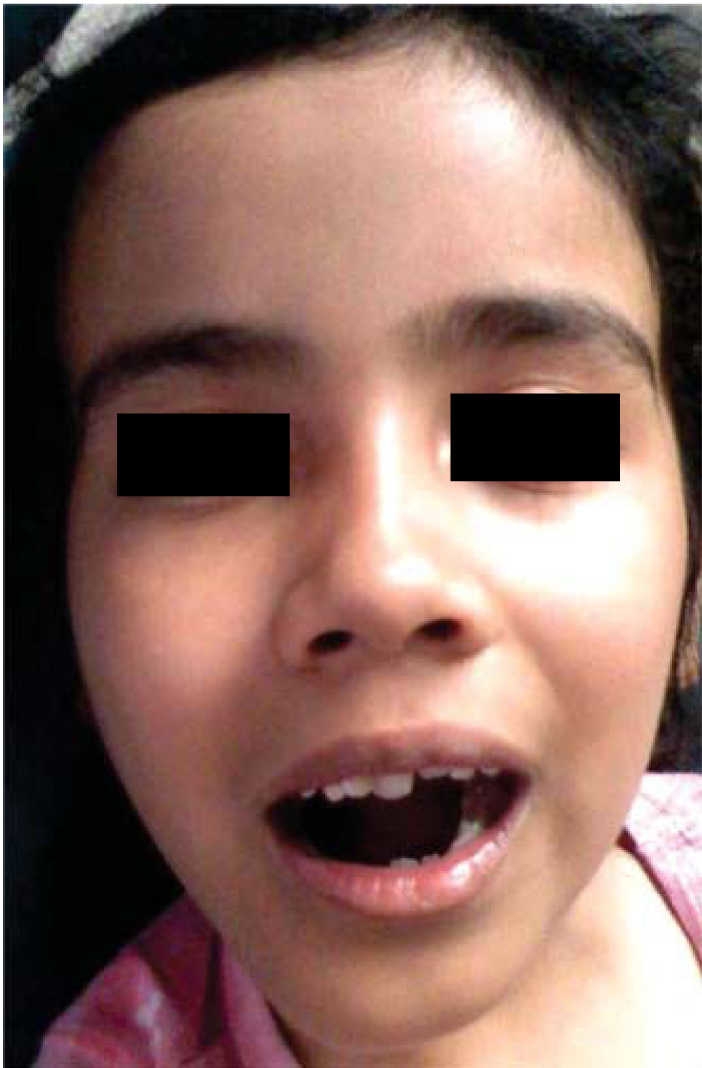

Eight year old female patient who attended the clinic with increase in left hemi-mandibular volume. Lesion was of a 5 month evolution with fast, painful growth (Figure 6). Intra-orally, expansion of vestibular cortical bone was observed, with tooth displacement (Figure 7). X-rays revealed a lesion destroying part of the body and ramus on the left side of the mandible, nevertheless, condyle and coronoid apophyses were preserved (Figure 8). The patient did not exhibit any other relevant data; laboratory exams yielded normal parameters. Result of incision biopsy was mandibular plexiform ameloblastoma. Block excision was undertaken in view of the lesion's local aggressive behavior (Figure 9). A reconstruction prosthesis was placed with preservation of condyle and coronoid apophyses (Figure 10). No complications were observed during post-operative period; motor and nerve structures were preserved. The patient exhibited suitable oral opening and appropriate facial appearance (Figure 11).

In these lesions, treatment of choice should be extensive resections, and whenever possible, early reconstruction of the damaged area,18 trying, whenever possible, to preserve nerve, sensory and motor structures. In three out of the four presented cases lower dental nerve continuity was preserved, and in one of them spontaneous mandibular bone formation could be observed,following the contour of the reconstructive titanium plate; titanium is a material that somewhat favors this type of reactions and is therefore recommended for this type of procedures instead of using chrome-cobalt plate. Severe loss of mandibular bone tissue was observed in cases 1 and 2. Patients’ relatives did not accept harvesting and placing of iliac crest graft to reconstruct damaged area. In this sense, it would be relevant to note that this decision was made in view of the impossibility of patients to continue with rehabilitation after bone graft procedure; this rehabilitation would involve implant placement in the area of the graft, therefore, partial reconstruction was decided upon. Most government hospitals in Mexico lack implant placement services, therefore, in these cases, reconstruction can only be partial. It is difficult for patients to avail themselves to these possibilities due to the high cost they represent when treated in private practice. There is much to be still furthered in the rehabilitation, not only physical but also physiological, of these patients. With respect to physical rehabilitation, availability to new advances such as bone regeneration with morpho-genetic protein-type bone inductors should be considered in order to avoid morbidity caused by all tumor harvesting and placing procedures.19 After surgical treatment is completed, the need for psycho-social therapy must be considered, since for the patient, to lose part of their anatomy, the face being the most affected, causes significant psychological damage.